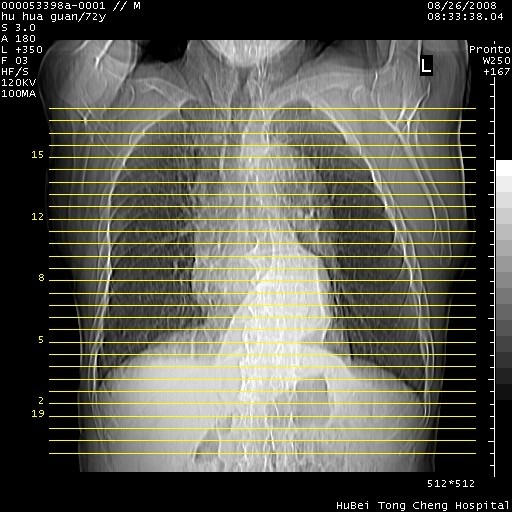

图像及窗宽窗位均不理想。周围性肺癌/胸腔积液/纵隔积液。

1、右肺周围性肺癌、胸腔积液(双)

2、建议食道吞钡和增强检查排除食道和主动脉病变

3、后纵隔淋巴类肿瘤